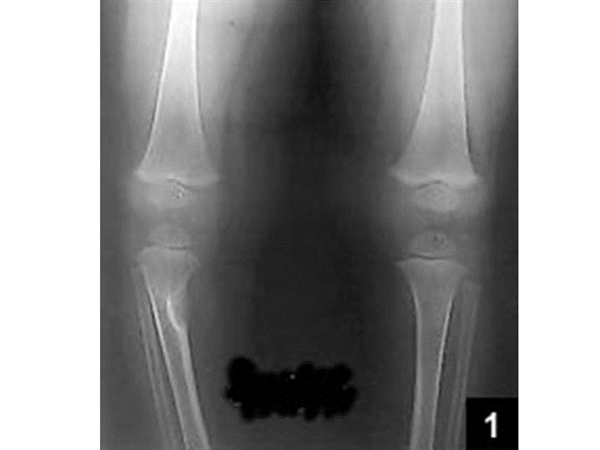

Focal Fibrocartilaginous Dysplasia (FFCD)

Atypical radiographic appearance of tibial FFCD. Radiolucent area in ...

Figure 1 from Focal fibrocartilaginous dysplasia of the tibia ...

Frontiers | Tibial deformities caused by focal fibrocartilaginous ...

Diagnosis and treatment of focal fibrocartilaginous dysplasi ...